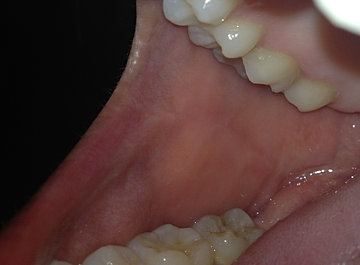

MEJILLAS

Se conocen también como carrillos, dan forma a las paredes laterales de la cavidad oral. su limite anterior son los labios. La superficie externa de las mejillas está recubierta por piel, mientras que en su cara interna está revestida por mucosa yugal, esta mucosa es  lisa, rosada y húmeda, su epitelio es plano estratificado no queratinizado, pero se puede observar a nivel de los molares una línea de oclusión de color blanquecino, con un epitelio paraqueratinizado.

La lámina propia está formada por tejido fibroelástico bastante denso y en la submucosa encontramos fibras elásticas,  vasos sanguineos y nervios ademas de  tejido adiposo y glándulas salivales.

En las mejillas a nivel del segundo molar superior podemos encontrar la desembocadura el conducto de Stenon de la glándula Parótida, en esta zona es posible encontrar otras glándulas de secreción sebácea aisladas que reciben el nombre de cuerpos de Fordyce, las podemos observar como zonas de color amarillo pálido.